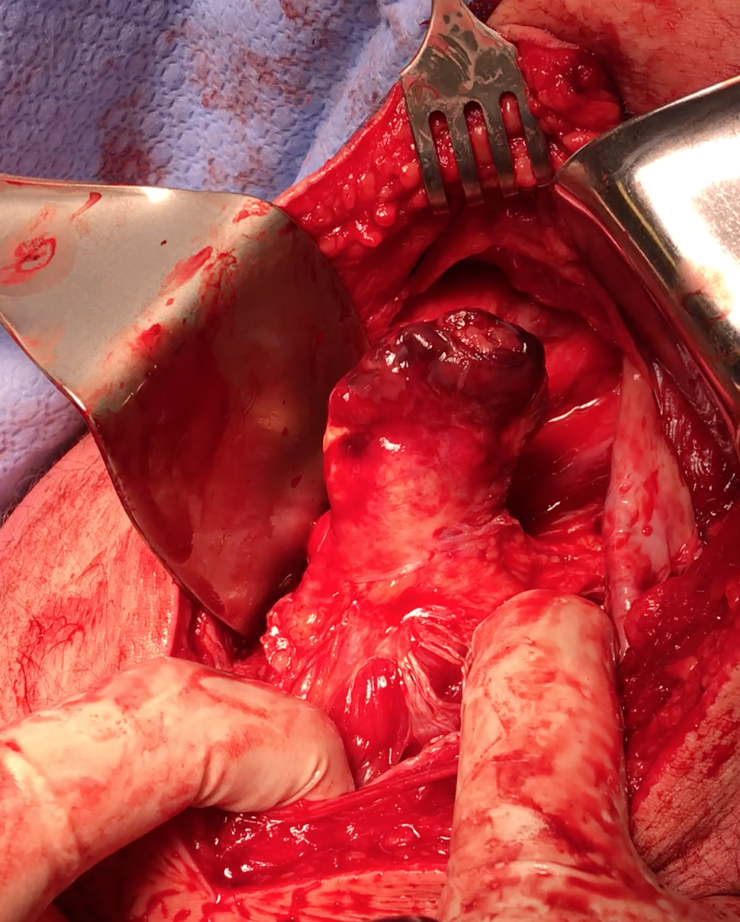

Exposing ischial tuberosity (*) with Cobb retractor

Ischial tuberosity exposed, then achilles bone block secured with screw